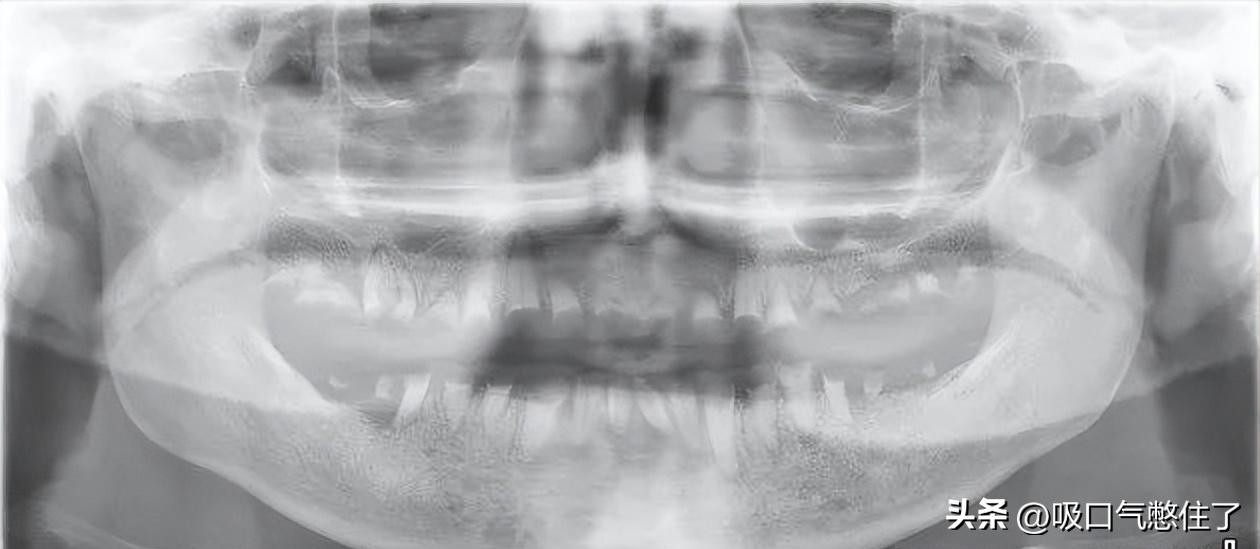

“冰毒嘴”口腔全景图像

“冰毒嘴” 的特点是严重的蛀牙和牙龈疾病,经常导致牙齿变黑、变色、腐烂、碎裂和脱落。其口腔全景图像表现如下:

图1 30岁女性,长期静脉注射毒品史。

口腔全景图显示大量牙齿缺失,大面积龋齿侵蚀所有剩余牙齿的牙冠,多处可见残留的牙根碎片和根尖脓肿。